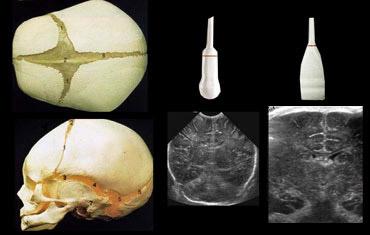

Sử dụng cả đầu dò sector và đầu dò tuyến tính, khảo sát qua thóp lớn và nếu cần thiết, qua cả thóp nhỏ và thóp bướm.

Không nên giới hạn bản thân chỉ sử dụng một loại đầu dò hoặc chỉ một cửa sổ âm học duy nhất (hình).

Thông thường, thóp lớn được sử dụng làm cửa sổ âm học.

Tuy nhiên, thóp nhỏ là cửa sổ âm học tốt để khảo sát thùy chẩm.